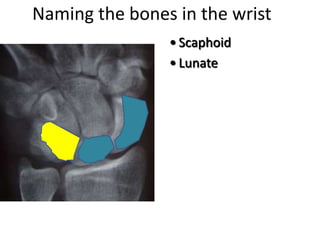

- Naming the bones, joints, tendons, nerves and skin landmarks of the hand and wrist.